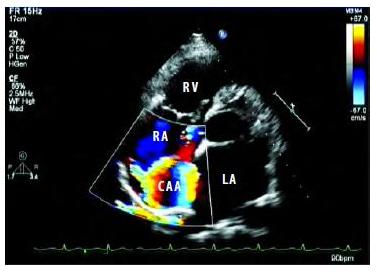

D型超声成像系统:又称频移诊断法,即接收频率与发射频率之差,又称多普勒频移。目前可分为脉冲式多普勒、连续式多普勒、高脉冲重复频率式多普勒、多点选通式多普勒以及彩色多普勒血流显像五种。